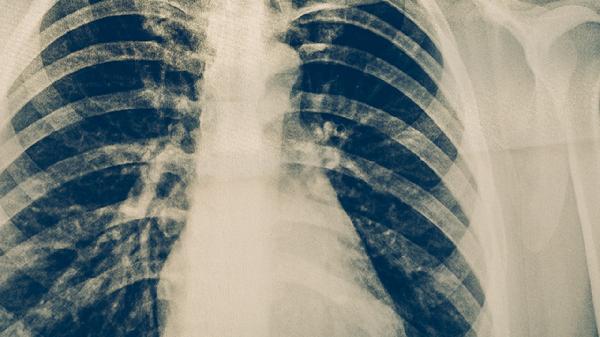

支气管肺炎恢复期需保证每日2000毫升水分摄入,可饮用温蜂蜜水或梨汁缓解咽干。饮食应遵循少量多餐原则,避免辛辣、油炸及过甜食物刺激呼吸道。适当增加富含ω-3脂肪酸的深海鱼类,如三文鱼、鲭鱼等,其抗炎成分有助于减轻肺部炎症。同时配合富含益生菌的发酵食品如无糖酸奶,调节肠道菌群增强免疫力。若出现持续高热或呼吸困难,应及时复查胸部影像学评估病情进展。